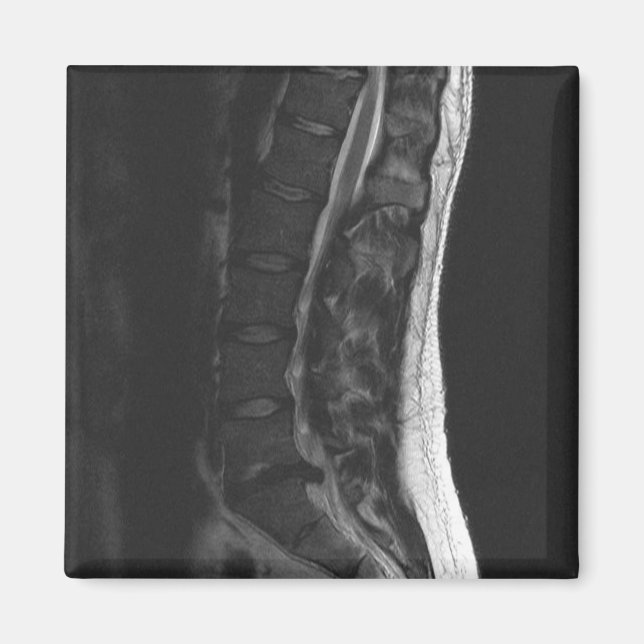

Jag förvandlade min MRI till en kylmagnet! Detta visar min L5-S1-skiva som har brutits. Det kommer alltid att påminna mig om användans rätta hållning och böjning vid knäna! Låt inte det här hända dig.. Jag har haft två operationer för att rätta till det.

brutendiskmritillbakaryggradmedicinskkirurgiskelett